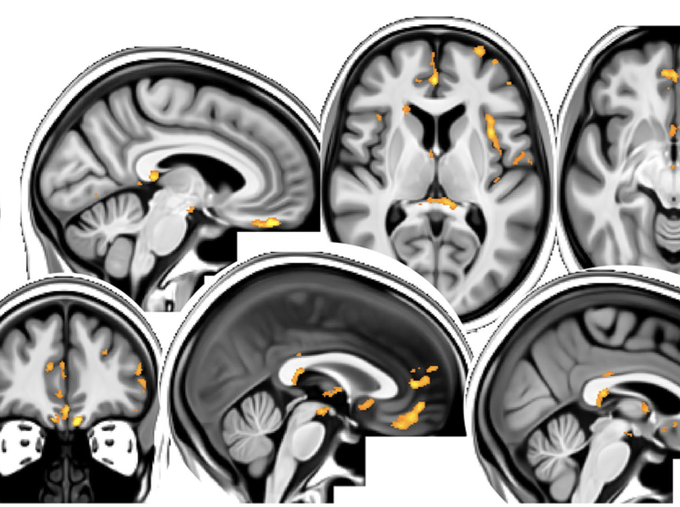

Hirn-Scans von SARS-CoV-2 Infizierten zeigen auch bei milden Verläufen Abnahme grauer Substanz in wichtigen Regionen. Infizierten Teilnehmer wiesen auch stärkeren kognitiven Abbau auf. Ob Auswirkungen wieder rückgängig gemacht werden können ist unklar

https://t.co/zvwdrbB4ZV